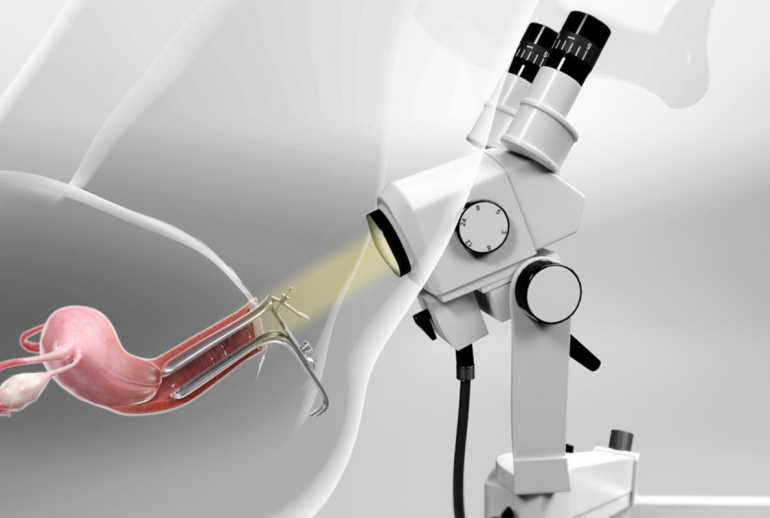

کولپوسکوپی یک فرآیند ساده و غیرتهاجمی است که توسط یک دستگاه به نام کولپوسکوپ انجام میشود. این دستگاه شامل یک میکروسکوپ با نور شدید است که به پزشک اجازه میدهد تا بافتهای دهانه رحم و واژن را با دقت بسیار بالا مشاهده کند. کولپوسکوپی معمولاً پس از انجام تست پاپ اسمیر غیرطبیعی توصیه میشود تا بررسی دقیقتری انجام شود و در صورت نیاز، نمونهبرداری (بیوپسی) از بافتها صورت گیرد.

- مشاهده با کولپوسکوپ: کولپوسکوپ به دهانه واژن نزدیک میشود، اما وارد بدن نمیشود. پزشک با استفاده از این دستگاه بافتها را با بزرگنمایی مشاهده میکند.